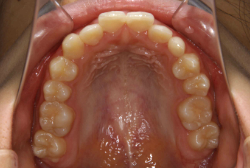

急速拡大装置を1日1回装置の中央にある拡大ネジを、ご自身で回して頂くことで25日間くらいかけて、6mmほど拡大しました。拡大後は、上顎の前歯の隙間が広がっていることがお分かりいただけると思うのですが、土台の骨ごと広がるのでこのような隙間ができます。その後1年半くらいマルチブラケット装置を使用して、全体の修正を行いました。

結局、歯の本数を減らすことなく、すべてご自分の歯を残して正しい配列にすることができました。このケースの場合、2009年10月より拡大と経過観察を行い、2012年3月より1年2ヶ月マルチブラケット装置を装着、2013年5月に治療を終了しました。2段階で行う治療としては短期間で終了しているケースと思います。